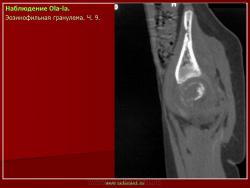

LCH у 9-летнего мальчика. На рентгенограммах локтевого сустава, в области дистального метафиза плечевой кости визуализируется литическое поражение с вовлечением кортикального слоя кости и периостальной реакцией (с признаками агрессивности).

LCH у 9-летнего мальчика.  Аксиальная КТ лучше отображает разрушение кортикального слоя кости (стрелка).

LCH у 9-летнего мальчика.  МР изображение регистрирует интрамедуллярное поражение с экстрамедуллярным увеличением мягких тканей (стрелки) и «агрессивным» периоститом (стрелка).